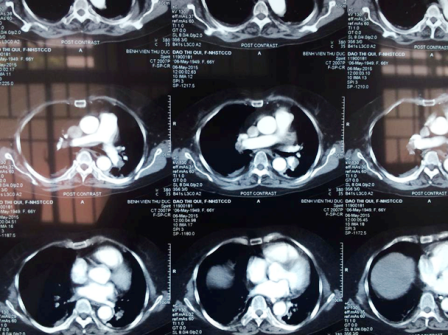

Khai thác bệnh sử ghi nhận, bệnh nhân bị thoát vị đĩa đệm cột sống thắt lưng. Một tuần trước đó, bà Quý đã trải qua cuộc phẫu thuật nẹp vít cột sống thắt lưng. Ngay lập tức khoa Hồi sức Tim mạch tiến hành khám lâm sàng và làm các xét nghiệm cận lâm sàng chẩn đoán. Kết quả siêu âm tim cho thấy, bệnh nhân suy tim phải cấp với thất phải dãn lớn và tăng áp động mạch phổi nặng; chụp CT ngực cản quang ghi nhận huyết khối gây tắc động mạch phổi 2 bên.

Sau khi hội chẩn, bác sĩ kết luận, bệnh nhân bị thuyên tắc động mạch phổi cấp gây rối loạn huyết động. BS Duy Lạc nhận định, tình trạng trên có thể là do cục máu đông hình thành tại vết mổ cũ di chuyển vào động mạch phổi gây tắc nghẽn. Trên cơ sở đó, người bệnh được chỉ định điều trị cấp cứu bằng thuốc tiêu sợi huyết.